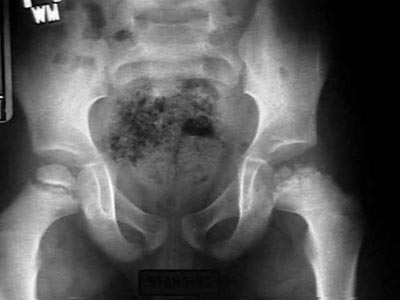

Legg-Calve-Perthes_Disease (5).jpg

الأمراض المشابهه D.Dx.

الاختبارات المعملية:

o اختبار كامل للدم .- -

o عامل ترسيب الدم قد يكون عالي في حالة وجود التهاب جرثومي .

o صور الاشعه تكون واضحة في هده الحالة .

o صور الاشعه في وضع ساقي الضفدعة تكون مفيدة للتشخيص .

o بناء على مكان ونسبة وجود تكلسات بمركز نمؤ رأس عظمة الفخذ تكونت عدة تقسيمات أكاديمية :

- 1-توقف نمؤ رأس عظمة الفخذ وصغر حجمه.

-2- كسور دقيقة تحت الطبقة الغضروفية للرأس.

-3- تنخر العظم بالرأس.

-4- تكون عظم جديد وتكلس هده التجمعات الجديدة للعظم .

-5- أخيرا مرحلة الشفاء .

- صور العظم بالمواد المشعة تبين حدود الانسداد بالدورة الدموية برأس العظم .